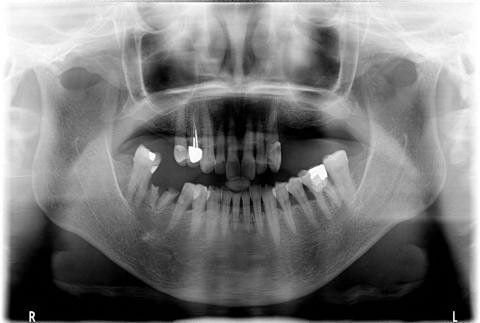

赖仁发教授经典案例:没有条件种,创造条件种

赖仁发教授经典案例:“沙漠”上创造出绿洲

种植体有长,有短,有细,有粗

因为种植牙,生活更美好